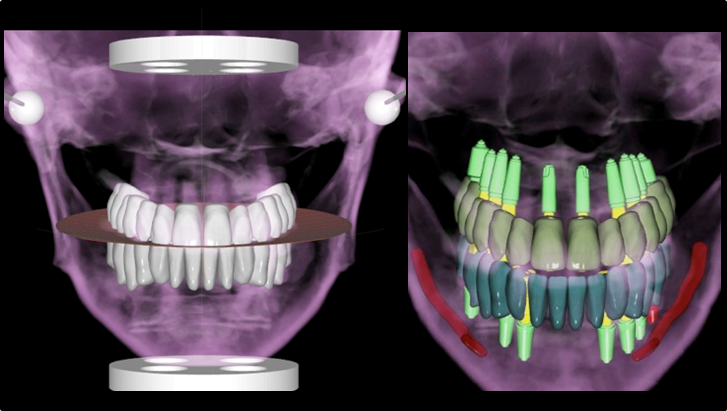

Effective R2STUDIO in complex tooth positioning

- Courtesy of Dr. Jong Cheol Kim, Korea

Dr. Jong Cheol Kim, edentulous, digital full-mouth prosthetics, digital guided surgery, guided surgery,R2 Studio, R2GATE Digital Oral Design, R2GATE DOD,flapless, AnyRidge, R2GATE, R2GATE full surgical Kit

AnyRidge implant system, R2GATE Guide, R2GATE surgical kit, R2GATE DOD, R2 Studio